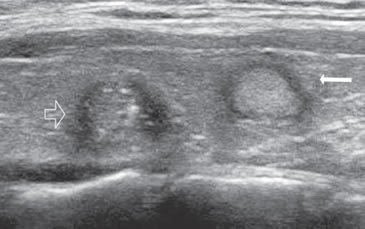

Figura 18. a) Tres nódulos coloideos, con aspecto

espongiforme, isovasculares al “doppler color”.

La flecha indica un espacio quístico y la flecha

abierta indica un pequeño tabique hiperecogénico.

La alternancia de ambos, forma este aspecto

en “panal de abeja”; b) y c) Nódulo coloideo

con aspecto espongiforme, con espacios quísticos

de mayor tamaño, de forma redondeada, que

aparece hipervascularizado en las áreas sólidas;

d) Nódulo coloideo mixto, predominantemente

quístico, en que el componente sólido conserva el

aspecto espongiforme (flecha abierta).